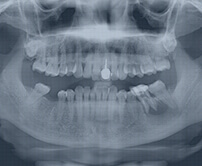

患者診斷

牙體牙髓醫生通過CT、X-ray檢查,確認有牙髓感染後,再決定進行杜牙根。